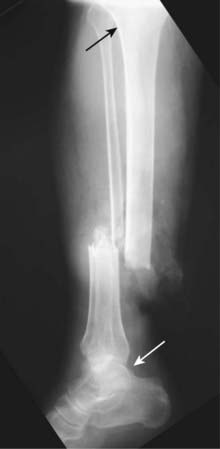

Figure 22-9 Rotation.

An unusual abnormality in fracture positioning, almost always involving the long bones, which describes the orientation of the joint at one end of the fractured bone relative to the orientation of the joint at the other end of the fractured bone. To appreciate rotation, both the joint above and the joint below a fracture must be included, preferably on the same radiograph. In this patient, the proximal tibia (solid black arrow) is oriented in the frontal projection while the distal tibia and ankle (solid white arrow) are rotated and oriented laterally.